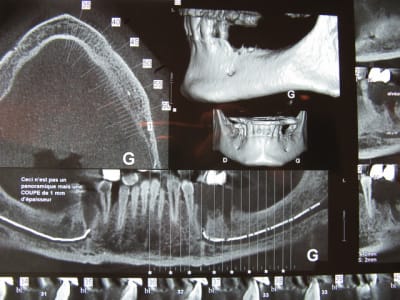

Pépé me demande de te fournir les documents ci joints , n'en abuse pas sauf si tu as prévu un voyage en Jamaïque .

;))))))